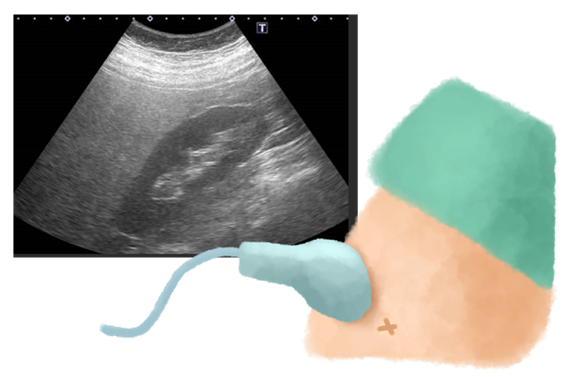

鉄則5:血液検査だけでなく腹部超音波(エコー)検査を定期的に受ける

採血結果が正常であっても、脂肪肝や肝硬変が進行していることがあります。脂肪肝の進行度や、肝臓の線維化(硬さ)を正確に知るためには、腹部超音波(エコー)検査が不可欠です。

- 腹部超音波(エコー)検査:痛みや被曝の心配なく、肝臓の脂肪の蓄積具合を軽度・中等度・高度の3段階で評価できます。脂肪が多い肝臓は「白っぽく」見えます。肝がんなどないかについても評価できます。

- 肝硬度測定:エコー検査と組み合わせて、肝臓の線維化(硬さ)の進行度を数値で評価できます。